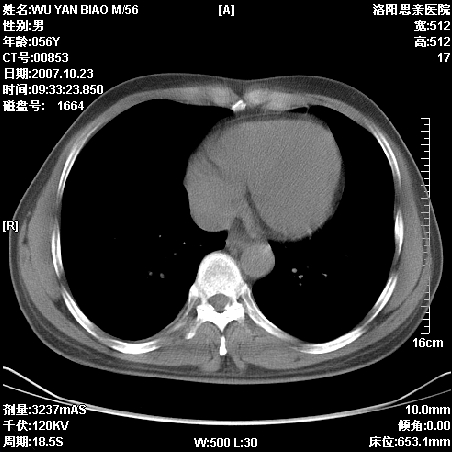

标题: CT10160:M56Y,体检发现,病人无不适,病人随访中

后上纵隔占位,与肺交界清,宽基底附着脊柱,密度均匀,局部骨质无明确改变.

考虑;神经源性肿瘤,---起源交感n链?,不除外肠源性囊肿.

1、病灶在后纵隔脊柱旁沟内,此处是神经原性肿瘤的好发部位

2、病灶边缘光滑整齐,更说明病灶来于纵隔,由于有胸膜的包裹所以才导致这么光滑的边缘

3、病灶内的密度均匀